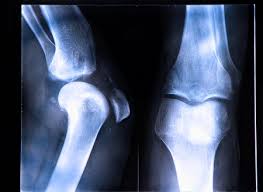

An acl tear or sprain occurs with a sudden change in direction or pivot against a locked knee. The acl — one of two ligaments that crosses the middle of the knee — connects your thighbone to your shinbone and helps stabilize your knee joint. The following anterior cruciate ligament reconstruction (aclr) guidelines were developed by the hss rehabilitation. Most acl injuries happen during sports and fitness activities that can put stress on the knee: A partially or completely torn acl is a common injury among athletes. The knee is essentially a hinged joint that is held together by the medial collateral (mcl), lateral collateral (lcl), anterior cruciate (acl) and posterior cruciate (pcl) ligaments. Posterior cruciate ligament (pcl) works with the acl. Acl injuries generally cause swelling, stiffness, and pain. Radiographic evaluation of anterior cruciate ligament (acl) reconstruction involves: Many times, a popping noise can be heard at the. An anterior cruciate ligament (acl) injury can be as complicated as the name sounds. A person who experiences an acute anterior cruciate ligament (acl) tear of the knee is likely to report some combination of the following knee symptoms: This increases the strain on the acl and places the ligament at risk.

It prevents the tibia from sliding out in front of the femur, as well as provides rotational stability to the knee, according to the american academy of orthopaedic surgeons. Most acl injuries happen during sports and fitness activities that can put stress on the knee: Femoral component a line is drawn along the posterior cortex of the femur a second line is drawn along the roof of the intercondylar notch of the femur (blume. Rehabilitative braces limit knee movement after an injury. Just like ice cream flavors, there are so many different types of knee braces to choose from.